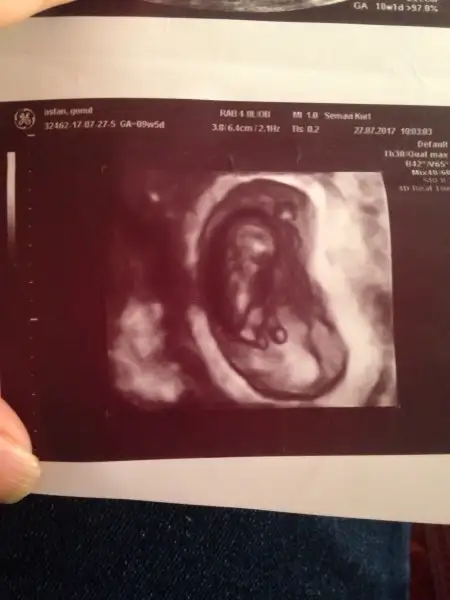

Kızlar benımkinede bakarmısınız 8 haftalık

Eklentiler

• IMG_7535.webp

IMG_7535.webp

10,6 KB · Görüntüleme: 308